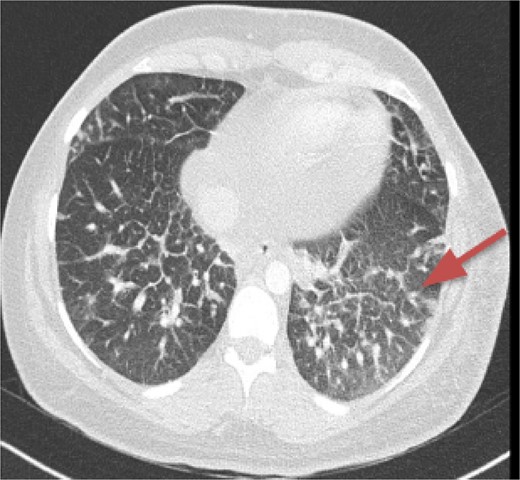

CT imaging, an anterior mediastinal mass was evident (Fig. 2), associated with the presence of thickening of interlobular septa in both lungs (Fig. 3). Surgery is carried out with diagnostic intent with suspicion of lymphoma vs DLP. A mass with cystic characteristics was found, thickening of interlobular septa and lymphatic channels that extended from the lung parenchyma to the mediastinum through the peribronchovascular space, dark serohematic pleural effusion without pleural lesions (Fig. 4).

The tomographic findings of DLP are interlobular septal thickening (70%), peribronchovascular interstitial thickening, ground glass opacities (80%), pleural effusion (40%), diffuse mediastinal infiltration (90%), and pleural thickening [2, 4], but no mediastinal mass is documented on CT. The radiological differential diagnoses of this disease are pulmonary edema, pulmonary veno-occlusive disease, pulmonary lymphangitic carcinomatosis, sarcoidosis, amyloidosis, primary pulmonary lymphoma, Erdheim-Chester disease, but these are not associated with mediastinal abnormalities [2].